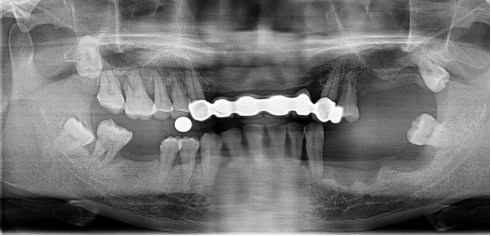

全口種植牙修復(fù)案例

病例簡介:

郭先生今年67歲,是位白手起家的成功企業(yè)家。早期忙碌的工作讓他疏于口腔保健,導(dǎo)致他上下牙列缺失。郭先生表示在二十年前在國外已經(jīng)做過種植牙,但是近期來我院就診時其之前種植牙的種植體已經(jīng)滑入到上頜竇內(nèi)。

“患者前牙骨量不足,壁薄,后牙因手術(shù)取出以前的種植體導(dǎo)致了骨頭的大量缺損,所以需要植骨才能進行種植牙手術(shù)。種植需要避開手術(shù)后的骨缺失區(qū),所以對種植體的承受力和穩(wěn)定性要求較高,同時患者對美觀要求較高?!眲⒈笤淌谠诹私饬嘶颊叩男枨笈c口腔情況后為他進行了植骨手術(shù),傷口愈合后,劉斌元教授為他進行CT掃描后確認(rèn)可以進行種植牙手術(shù)。

手術(shù)成功結(jié)束,郭先生的全口牙齒全部種上,郭先生表示種牙后感覺很好,使用起來很方便:“終于吃上了我喜歡的堅果了!”